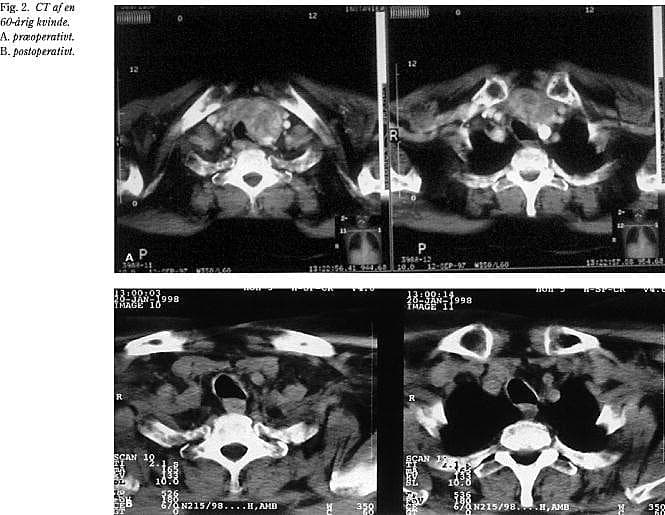

Røntgenundersøgelsen viste kompression af trachea i næsten alle tilfælde. Kun i to tilfælde med symptomer på øvre luftvejsobstruktion viste almindelig røntgenundersøgelse med forfra- og sideoptagelse ingen forsnævring. I de øvrige 31 tilfælde var der kompression af tracheas lumen i varierende grad, ofte med en betydelig dislokation. Den postoperative røntgenundersøgelse viste i alle tilfælde en betydelig bedring og en normalisering af tracheas lumen. Denne effekt indtraf hurtigt, undertiden i løbet af få dage, og subjektivt bedredes respirationen meget hurtigt, ofte i løbet af få timer (Fig. 1 og Fig. 2).